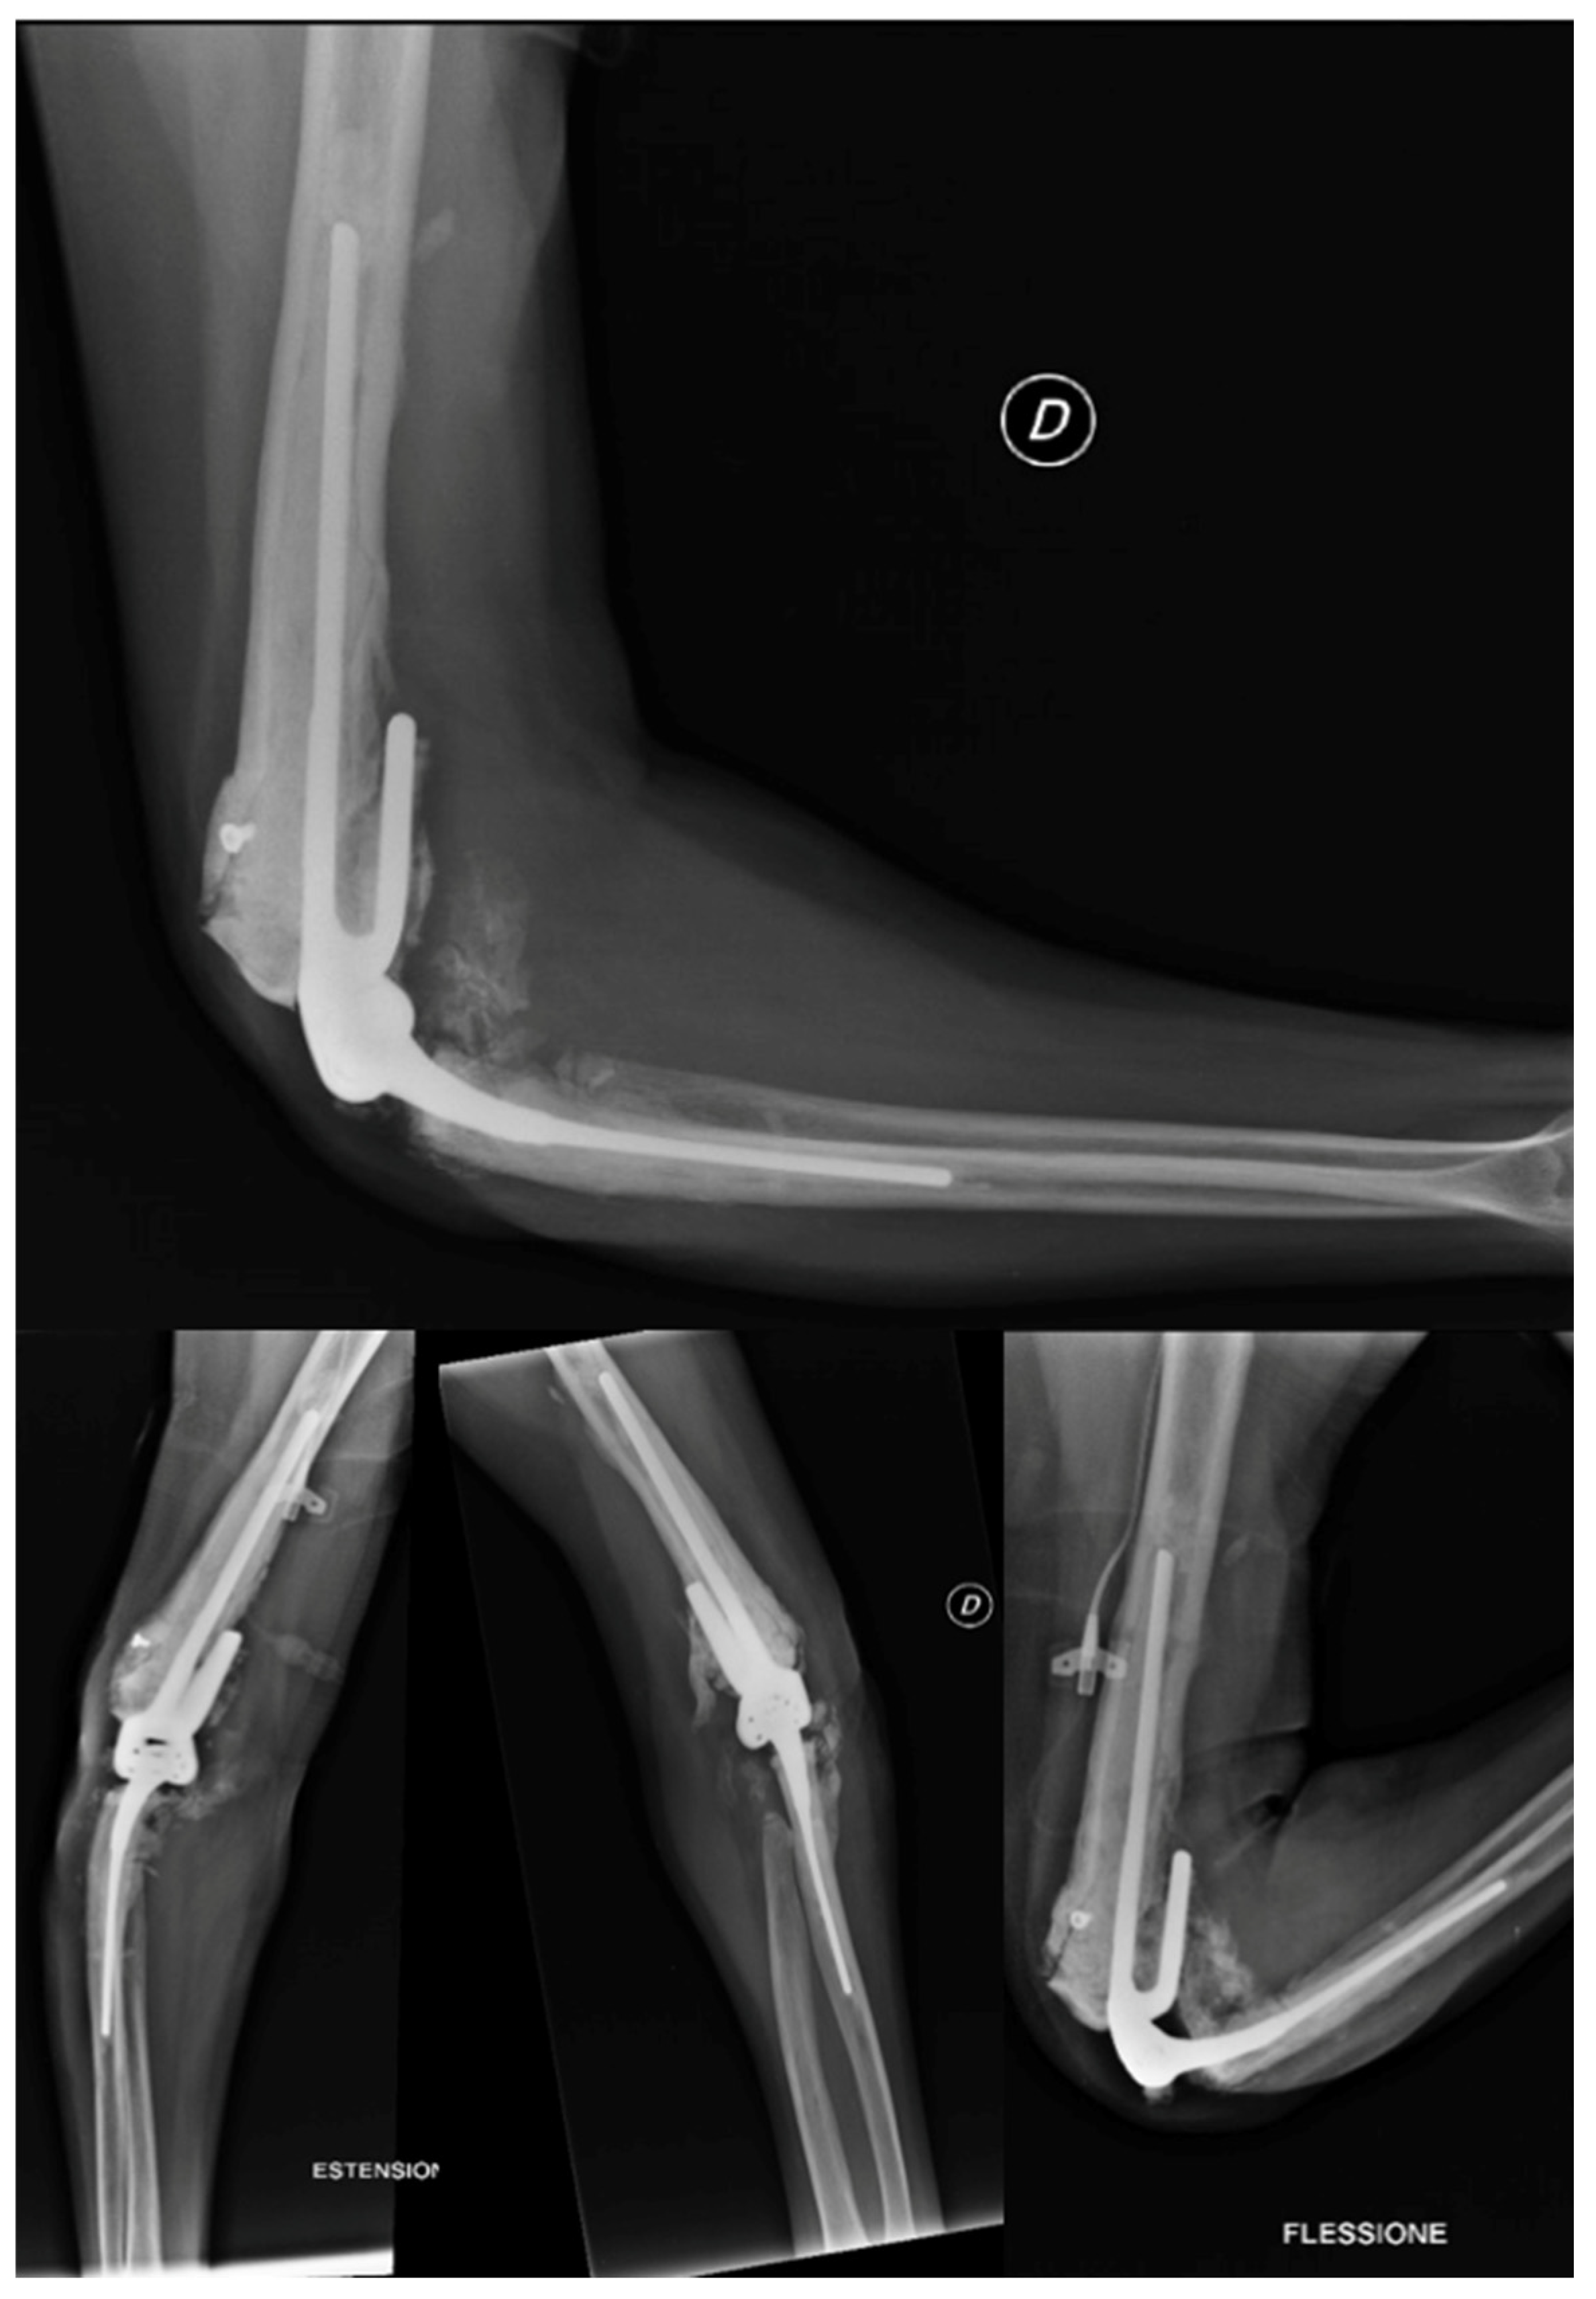

Due to the patient's clinical symptoms, a right elbow X-ray was performed (Figure 1), which revealed significant morpho-structural changes in the bone structures of the joint, with osteolytic areas of bone. The X-ray also showed calcification of the periarticular soft tissue and dislocation of the radial head. Additionally, the patient had an enlarging ulnar elbow mass, which was attributed to recurrent intra-articular bleeding that involved the periarticular soft tissue.

Figure 1. X-Ray anteroposterior and lateral views of the right elbow. First radiological presentation.